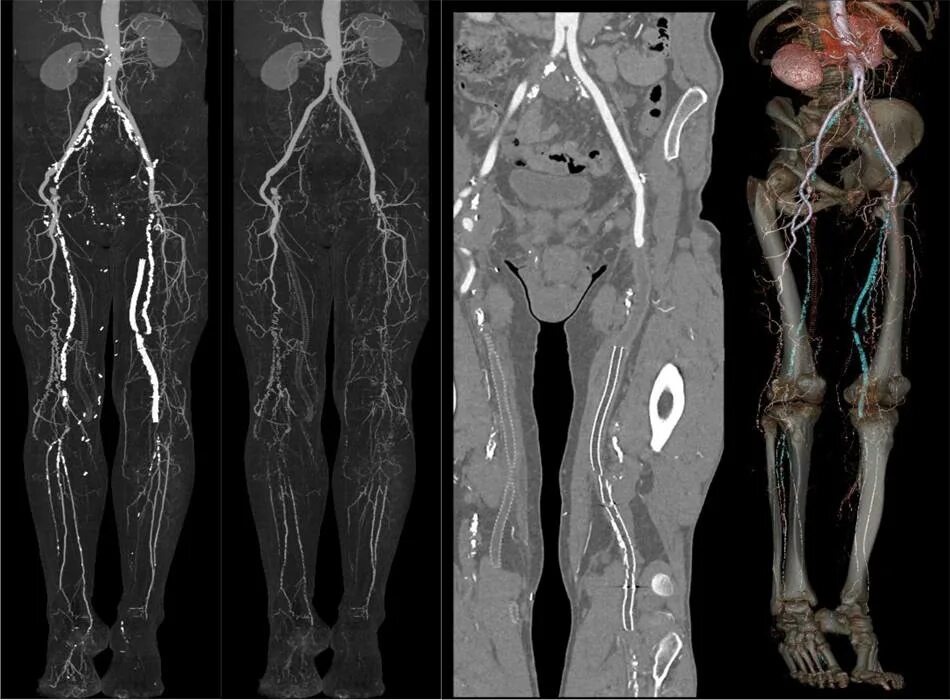

Как проходит кт всего тела